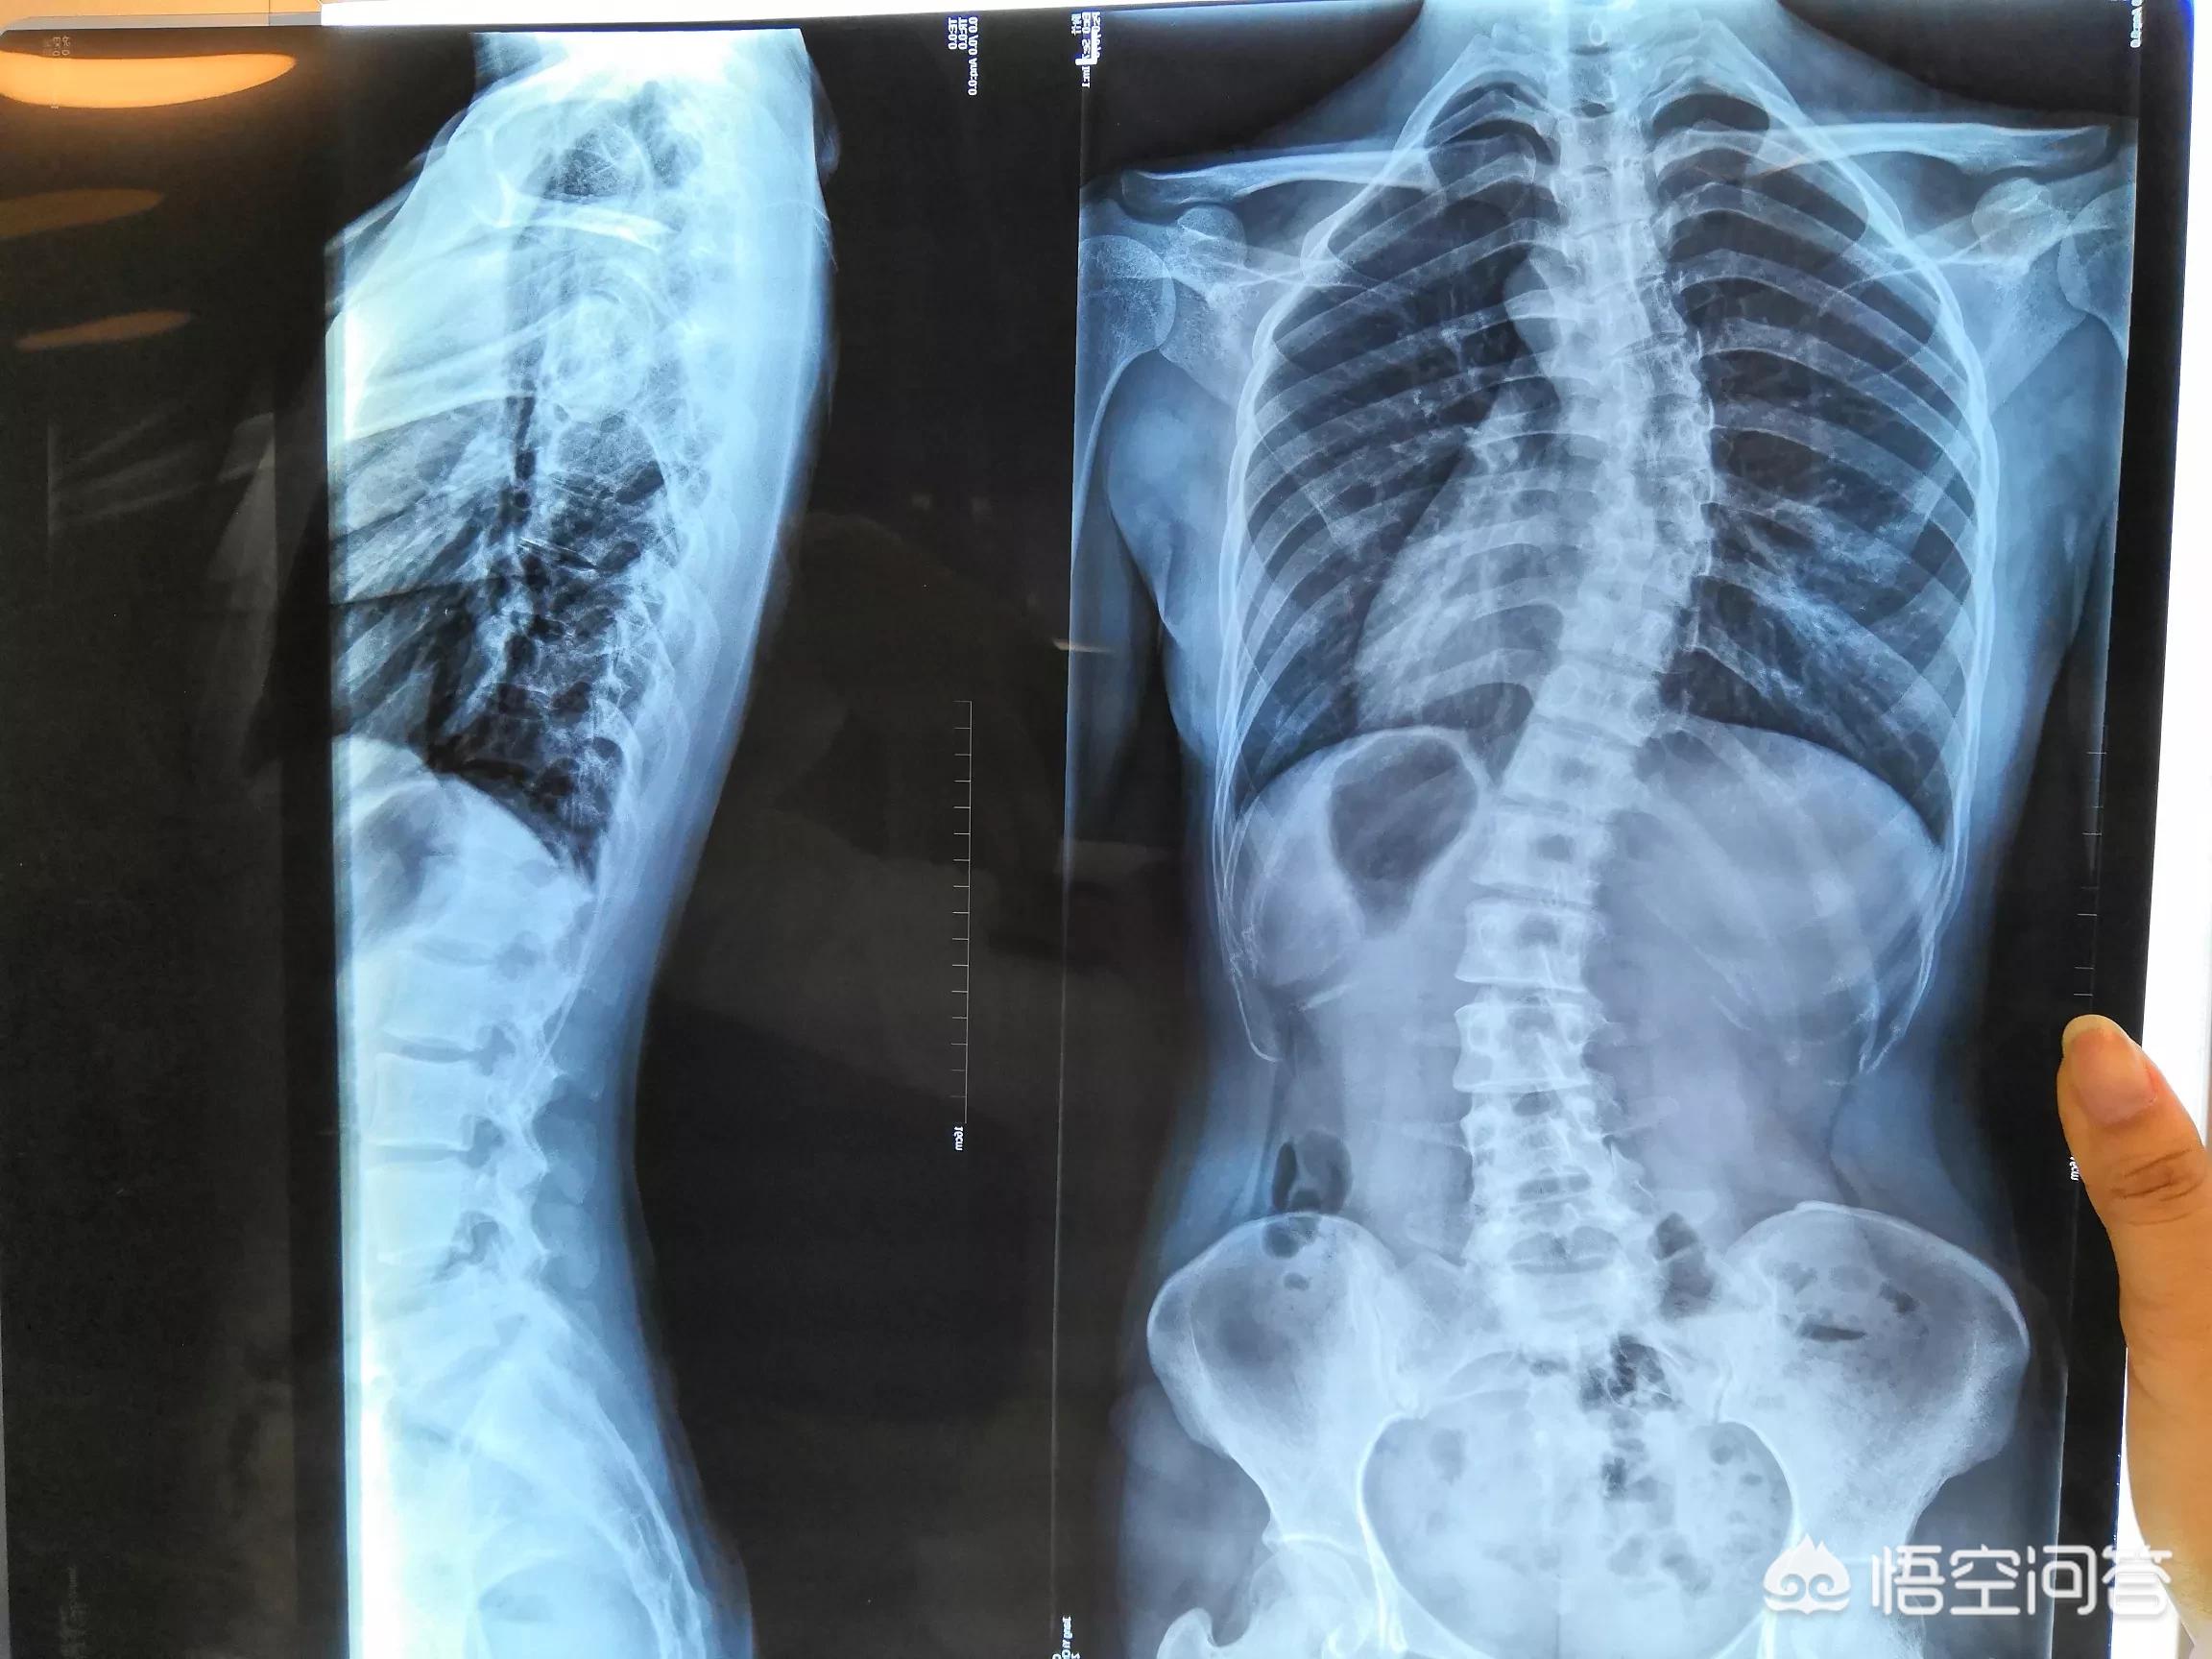

脊柱侧弯的确诊标注是站立位全脊柱正位x光片测量Cobb角大于10°,但是在实际检查中特别是小度数侧弯光看x光片无法准确评估,现在引入了背部旋转度标准,利用专用的旋转测量尺在标准体位下测量背部的倾斜度,如果旋转度大于5°,那么结合X光片就可以判断侧弯是真实的。如未测出旋转度,那么就需要排查是否因为站立姿态问题显示的x光异常。

第二、根据严重程度来分类。分为轻度、中度、重度以及极重度。Cobb角在40度到80度之间为中度的脊柱侧弯,Cobb角大于80度的往往是重度脊柱侧弯。小于40度的轻度脊柱侧弯可以通过保守治疗,例如支具、体育运动锻炼等等。40度到80度之间的中度脊柱侧弯,通过支具是没有太大的效果,有可能会影响到患者的心肺功能,需要考虑手术治疗。